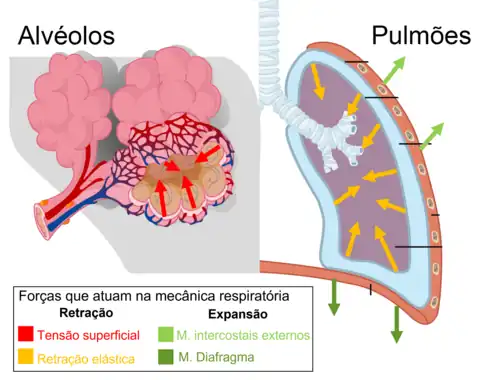

Forças Constitutivas (Estática Pulmonar)

O pulmão, a pleura pulmonar e a caixa torácica atuam conjuntamente na mecânica respiratória e cada uma possui propriedades estruturais singulares que determinam as forças constitutivas que atuam sobre elas.

O interstício pulmonar é composto de fibras colágenas e, de especial interesse, elastina - uma proteína que contém intensa atividade elástica, possibilitando a distensão do pulmão. Analogamente a uma fita elástica distendida, a elastina tende a "puxar" o pulmão para dentro, ou seja, a elastina produz uma força elástica de retração. A composição elástica do pulmão é central na determinação da complacência pulmonar. Fibroses pulmonares aumentam a concentração de elastina e provocam aumento demasiado da retração elástica do pulmão, dificultando a expansão durante a inspiração.[5]

Além disso, os alvéolos são revestidos por uma camada muito delgada de água, causando o aparecimento da tensão superficial como uma outra força de retração que tenderá a colapsar os alvéolos. Para evitar o colapso alveolar, células pneomócitos tipo II produzem surfactante pulmonar, diminuindo a intensidade da tensão superficial.

Não obstante, a tensão superficial da água alveolar e a força elástica de retração do interstício pulmonar formam as principais forças de retração pulmonar. De fato, é justamente devido à ação dessas forças que o pulmão tende naturalmente a se retrair. Caso seja retirado da caixa torácica, o pulmão imediatamente sofre desinsuflação e toma seu menor volume.[5]

Como a tendência natural dos pulmões é a retração, os músculos da respiração atuam em manter o volúme mínimo dos pulmões (volume residual) e são indispensáveis na expansão pulmonar durante a inspiração.

Os principais músculos da respiração são o músculo diafragma, inferior aos pulmões, e os músculos intercostais, distais aos pulmões. O diafragma, em especial, é o musculo mais importante da respiração, uma vez que participa tanto da inspiração, quanto da expiração e em respirações passivas e forçadas. Em condições patológicas, a exaustão dos músculos respiratórios deflagra insuficiência respiratória, levando à morte caso continuada.[8]